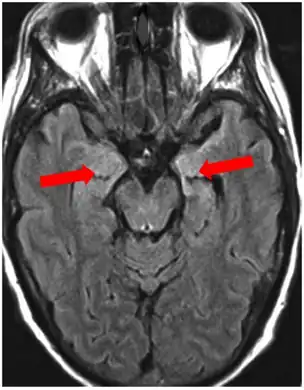

Neuroimaging

Brain MRI is the mainstay of initial investigation pointing to limbic lobe pathology revealing increased T2 signal involving one or both temporal lobes in most cases.[22][14]

Serial MRI in LE starts as an acute disease with uni- or bilateral swollen temporomesial structures that are hyperintense on fluid attenuation inversion recovery and T2-weighted sequences. Swelling and hyperintensity may persist over months to years, but in most cases progressive temporomesial atrophy develops.[23]